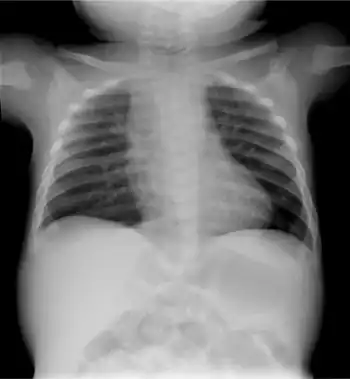

| Infant male with the brachytelephalangic type of chondrodysplasia punctata | |